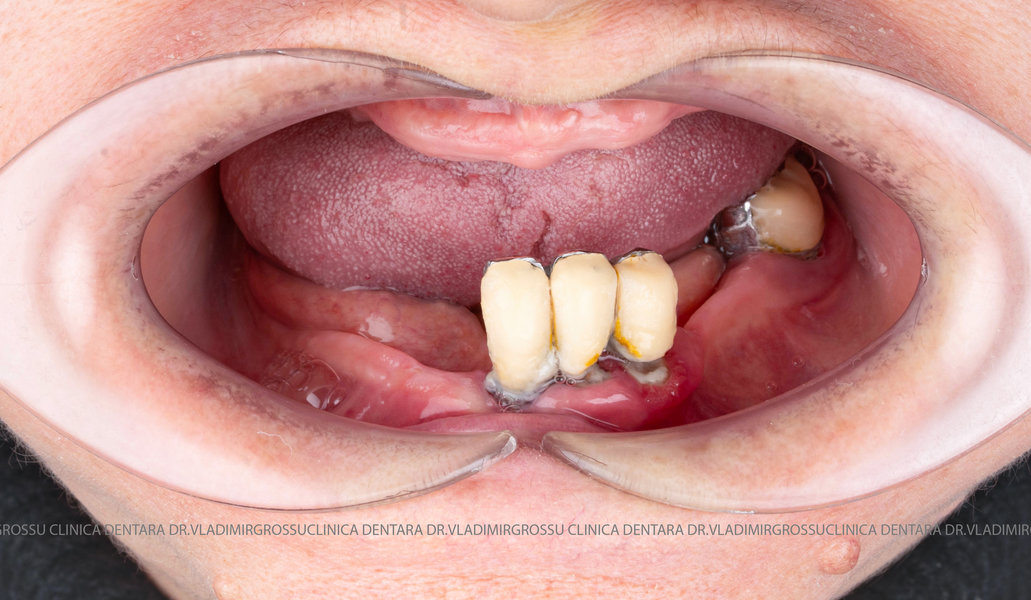

Această metodă este indicată pacienților cu edentație totală sau cu lipsuri dentare multiple, când dinții rămași nu mai pot susține o proteză fixă eficientă. Procedura se desfășoară în două etape:

- Prima etapă constă în inserarea implanturilor și fixarea unei proteze provizorii, realizate de obicei din masă plastică frezată, ce este montată în a doua sau a treia zi postoperator. Suturile sunt îndepărtate după 5-7 zile.